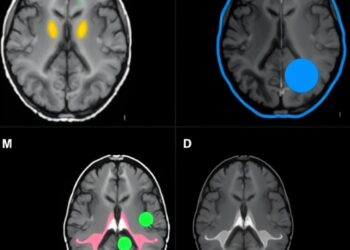

STN DBS fMRI Uncovers Symptom-Specific Brain Networks

In recent years, the therapeutic landscape for Parkinson’s disease has been significantly transformed by advances in deep brain stimulation (DBS), ...